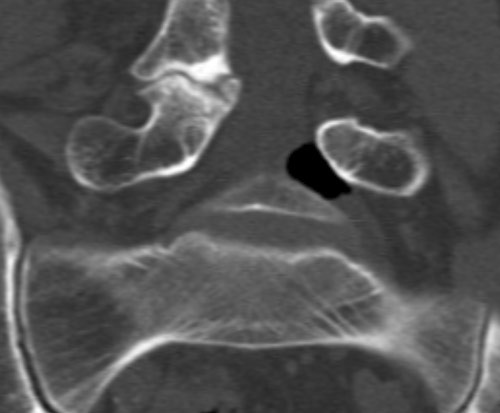

En mann i 60-årene ble innlagt med to dagers sykehistorie med venstresidig isjialgi og pareseutvikling i L5-innervert muskulatur. MR viste en oppfylling i venstre laterale recess i nivå L4/L5 med dorsal dislokasjon av venstre L5-rot. Oppfyllingen hadde uvanlig lavt MR-signal som ga mistanke om forkalkninger eller luft. Supplerende CT viste en velavgrenset luftansamling i samme område (bildene).

Klinisk forverring førte til kirurgisk eksplorasjon av L5-roten. Ventralt for denne så man en luftmengde innkapslet i epiduralt bløtvev, incisjon ble foretatt og luften sluppet fri. Etter dette var L5-roten mykere palpatorisk og hadde fritt forløp. Pasienten opplevde betydelig bedring postoperativt.

Hos vår pasient forelå bare lettgradig skivebukning uten ruptur i anulus fibrosus og lett fasettleddsartrose i aktuelle nivå. Luften kan representere gassomdanning av et sekvester fra en tidligere prolaps, alternativt pseudocyste assosiert med vakuumfenomen i tilstøtende skiverom. Det er vanskelig å forklare akutt innsettende sykehistorie på bakgrunn av dette, men incisjon og frigjøring av luftansamlingen hos pasienten var likevel terapeutisk.